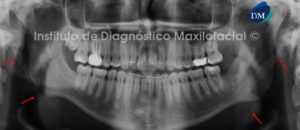

Paciente masculino de 15 años de edad que es referido por presentar alteración morfológica de las estructuras blandas y duras del sector anterior de los maxilares superiores. A la evaluación de la radiografía panorámica se observan defectos óseos (uno a cada lado distal de los incisivos centrales) que se extienden desde la cima del reborde alveolar hasta el piso de fosa nasal, comprometiendo este último (flechas rojas). Así mismo, se evidencia que los defectos óseos se encuentran asociados a la ausencia de las piezas 12 y 22; así como, a la presencia de dos piezas supernumerarias (flechas amarillas). Signos radiográficos compatibles con Paladar Fisurado Bilateral (Fig. 1).